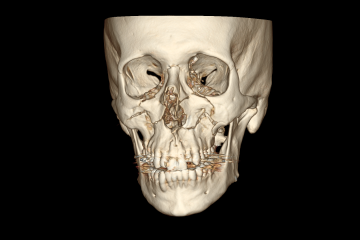

O maxilar quebrou em várias partes em ambos os lados da face. A parte da arcada dentária se soltou do crânio, ela recuou 7mm. Era visível a deformação, dava para sentir ela se acomodar quando eu falava.

Fiquei internado uma semana, a cirurgia para fixação dos ossos foi realizada com sucesso.

Essas são imagens da minha tomografia.